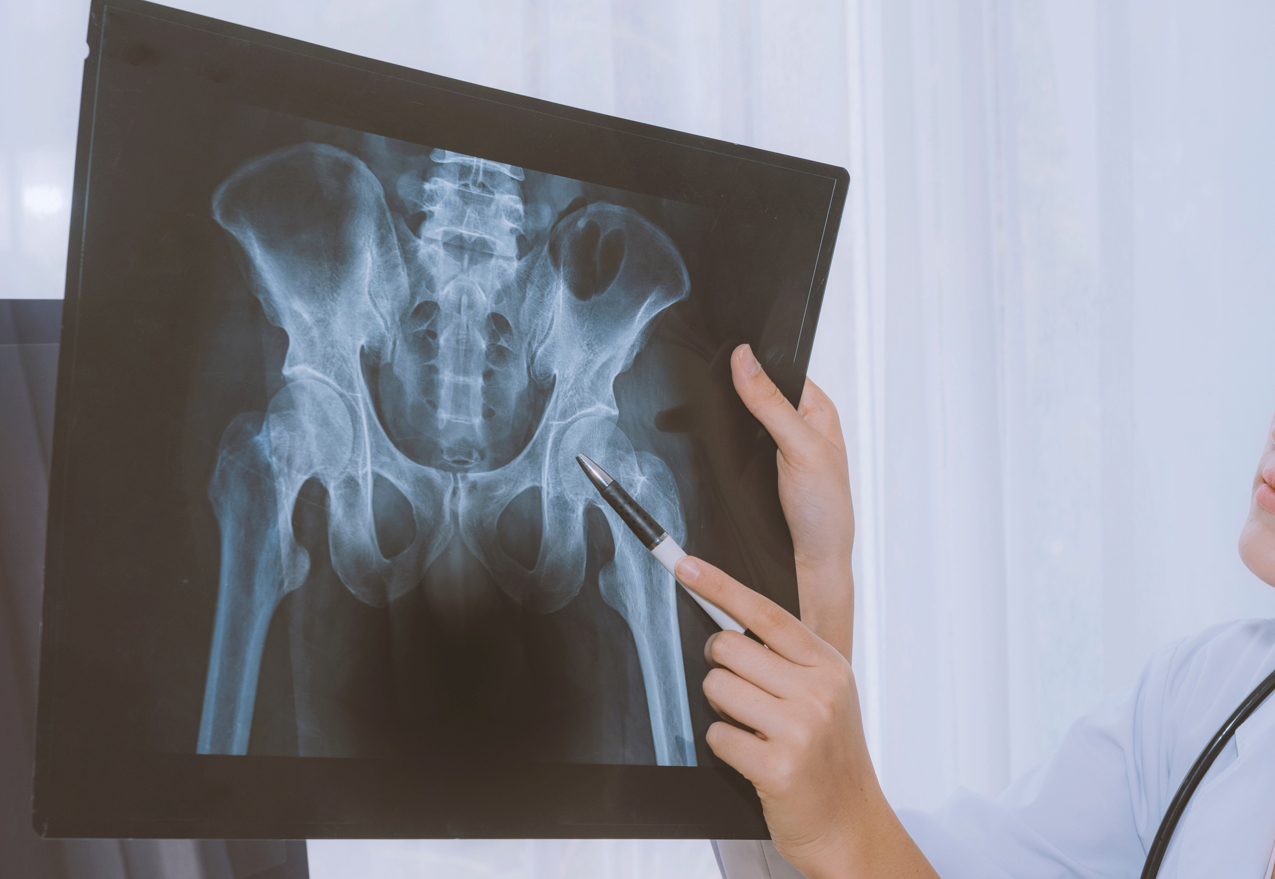

Nous avons la chance de le posséder la radiographie numérique à la Clinique Podiatrique St-Nicolas afin d'être plus précis dans nos diagnostics. N'hésitez pas à consulter notre podiatre pour toutes les douleurs des pieds et des chevilles.